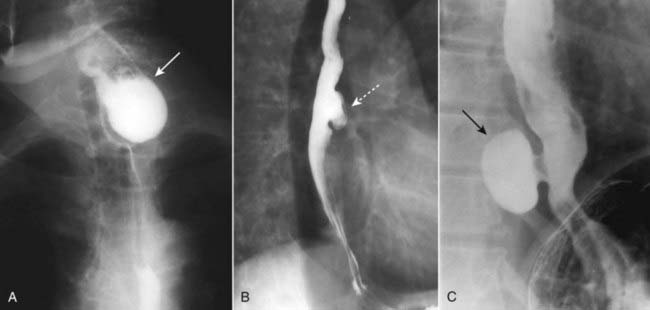

imageEsophageal diverticula occur in three locations: the neck, around the carina, and just above the diaphragm. In the neck, the diverticulum is posteriorly located and is called a Zenker diverticulum. Diverticula at the level of the carina may be due to extrinsic inflammatory disease like tuberculosis (traction diverticula); diverticula just above the esophagogastric junction are called epiphrenic diverticula (Fig. 18-3).

Figure 18-3 Esophageal diverticula.

Esophageal diverticula characteristically occur (A) in the neck from a localized weakness in the posterior wall of the hypopharynx (Zenker diverticulum) (solid white arrow); in the mid-esophagus (B) from extrinsic disease like TB that causes fibrosis, which pulls on the esophagus forming a traction diverticulum (dotted white arrow); or (C) just above the diaphragm in the distal esophagus (epiphrenic diverticulum) (solid black arrow). Only the traction diverticulum is a true diverticulum in that it contains all layers of the esophagus; the Zenker and epiphrenic are false or pseudodiverticula because the mucosa and submucosa herniate through a defect in the muscular layer.